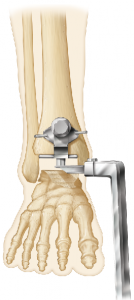

The Vantage tibial component maximizes the contact area on the prepared tibial plafond surface, featuring a recessed area to accommodate the fibula while maximizing tibial component cortical support. (Figure 1) To diminish joint fluid gaining access to the tibial component’s backside and creating component loosening, recent trends in TAA technique favor not violating the anterior tibial cortex.

(Figure 2) The Vantage’s technique confers the advantage of vertically oriented tibial component fixation in contrast to most other modern systems that utilize obliquely orientated tibial pegs to avoid violating the anterior tibial cortex or traditional horizontally oriented tibial fixation that require anterior tibial cortex penetration.

(Figure 3) Finite element modeling suggests that vertically oriented pegs provide ideal loading characteristics on the tibial bone-implant interface, thereby diminishing the risk of eccentric stresses, stress shielding and the chance of tibial component loosening.

(Figure 4) Moreover, the Vantage tibial component’s central cage, similar to the cage featured on the Advita reverse total shoulder system, affords not only reliable press-fit fixation but adds the potential for bone ingrowth and superior long-term fixation.